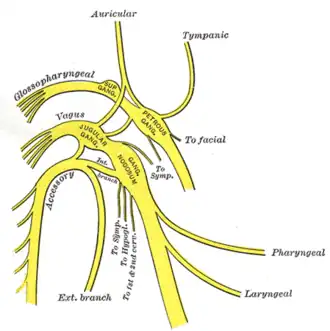

Plan of upper portions of glossopharyngeal, vagus, and accessory nerves. | |

Passing through the lateral funiculus of the medulla spinalis, they emerge on its surface and unite to form a single trunk, which ascends between the ligamentum denticulatum and the posterior roots of the spinal nerves; enters the skull through the foramen magnum, and is then directed to the jugular foramen, through which it passes, lying in the same sheath of dura mater as the vagus, but separated from it by a fold of the arachnoid.

In the jugular foramen, it receives one or two filaments from the cranial part of the nerve, or else joins it for a short distance and then separates from it again.

As it exits from the jugular foramen, it runs backward in front of the internal jugular vein in 66.6% of cases, and behind it in 33% of cases.

The nerve then descends obliquely behind the Digastricus and Stylohyoideus to the upper part of the Sternocleidomastoideus; it pierces this muscle, and courses obliquely across the posterior triangle of the neck, to end in the deep surface of the Trapezius.

As it traverses the Sternocleidomastoideus it gives several filaments to the muscle, and joins with branches from the second cervical nerve.

In the posterior triangle it unites with the second and third cervical nerves, while beneath the Trapezius it forms a plexus with the third and fourth cervical nerves, and from this plexus fibers are distributed to the muscle.